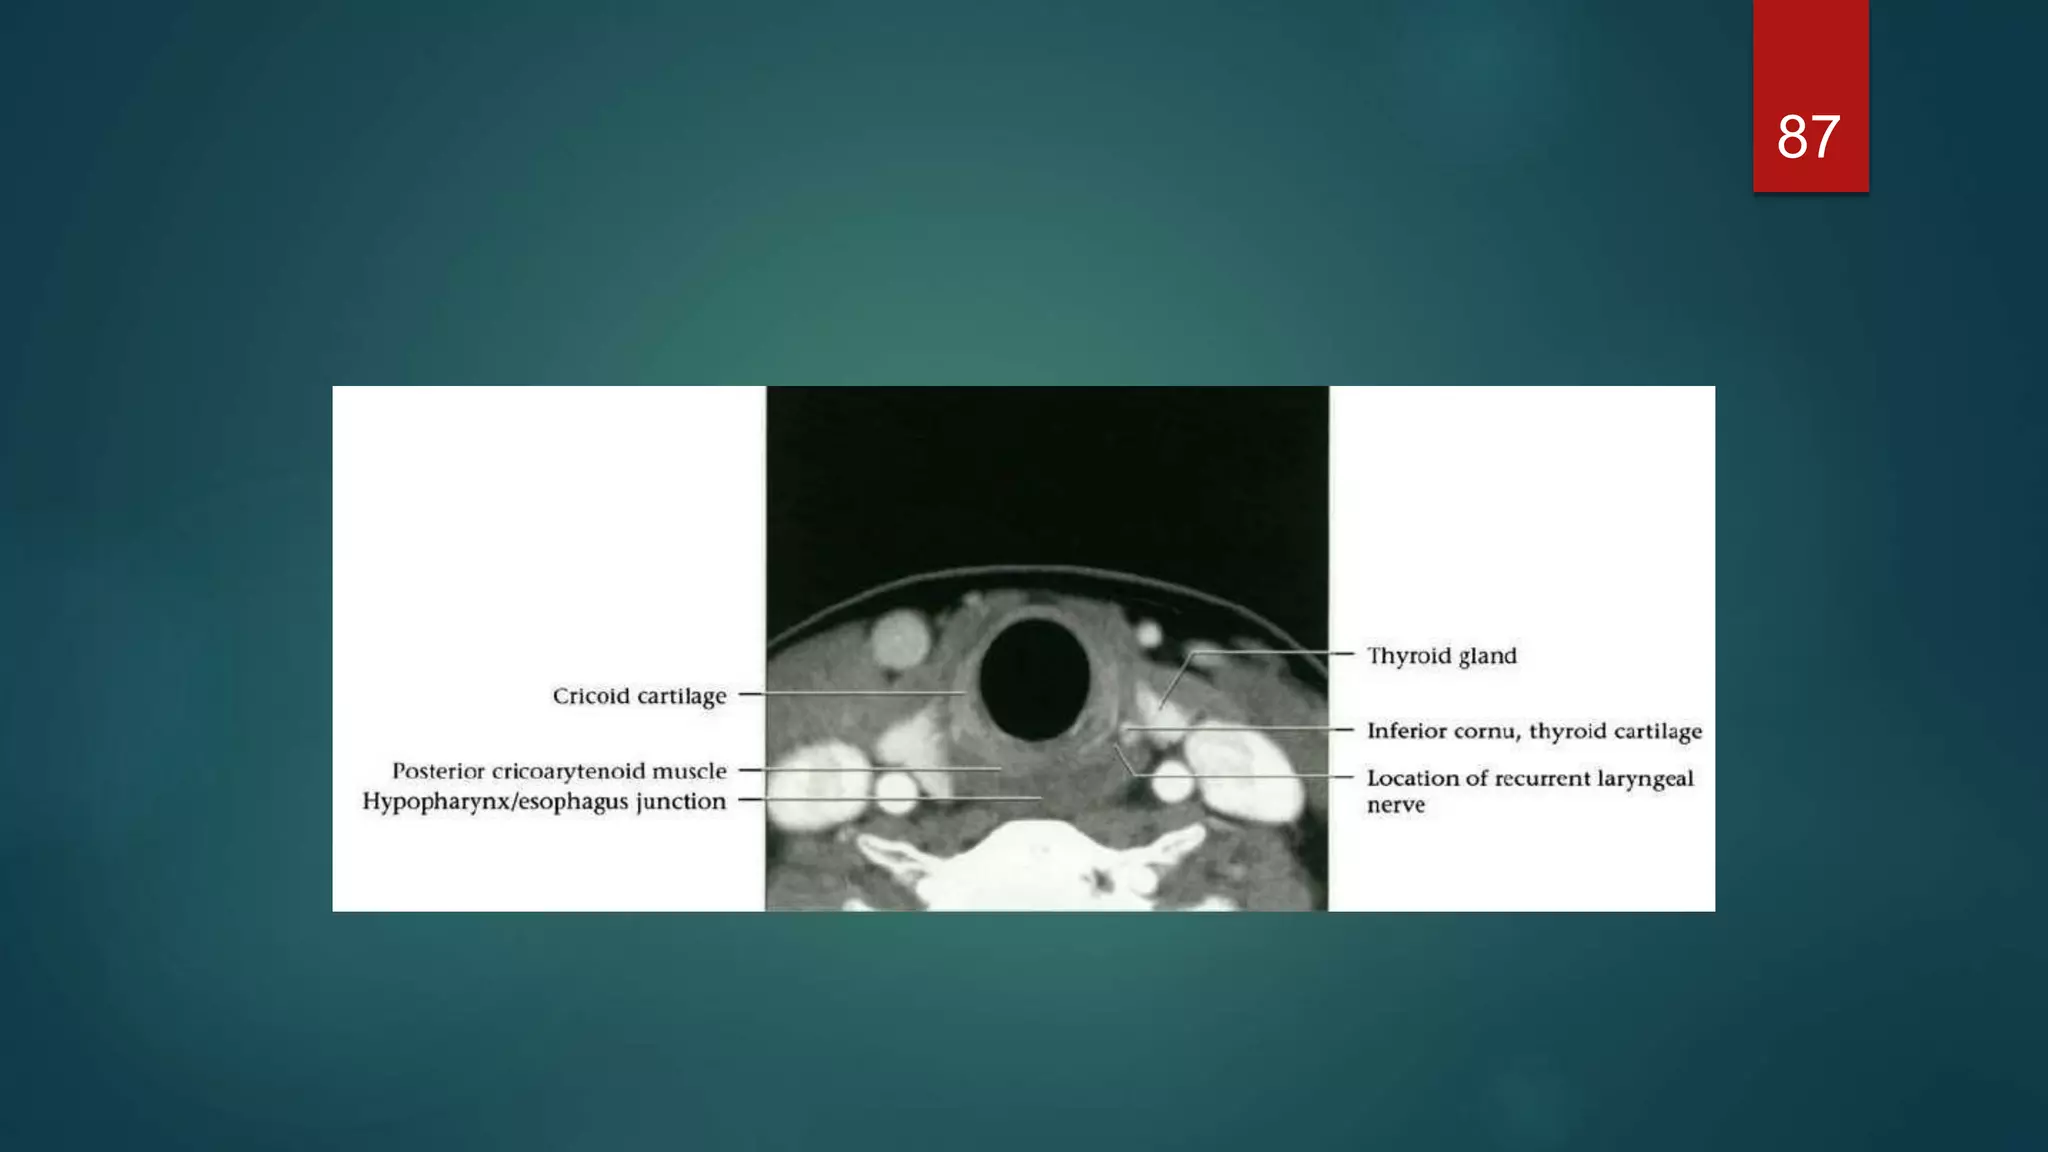

Infraglottic level

 Just below the cords the larynx is elliptical. The lamina of the cricoid is

posterior, with the cricothyroid membrane anterior.

 At a lower level the larynx is more circular and the cricoid forms a complete

ring. Part of the lobes of the thyroid gland may be seen laterally,

Infraglottic level  Justbelow the cords the larynx is elliptical. The lamina of the cricoid is posterior, with the cricothyroid membrane anterior.  At a lower level the larynx is more circular and the cricoid forms a complete ring. Part of the lobes of the thyroid gland may be seen laterally, 76